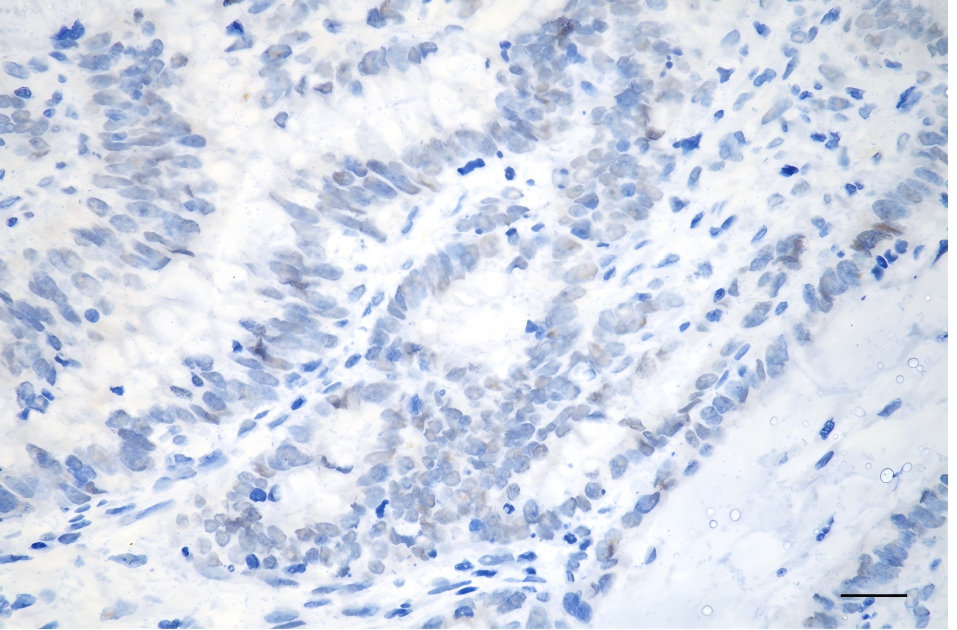

Immunohistochemistry was performed on paraffin-embedded human sigmoid colon carcinoma using GTF2I antibody. Antigen retrieval was done in sodium citrate buffer (pH 6.0). DAB was used for detection, with hematoxylin counterstaining. Images were acquired using a Nikon Ci-L Plus microscope (40× objective). Scale bar: 25 μm.